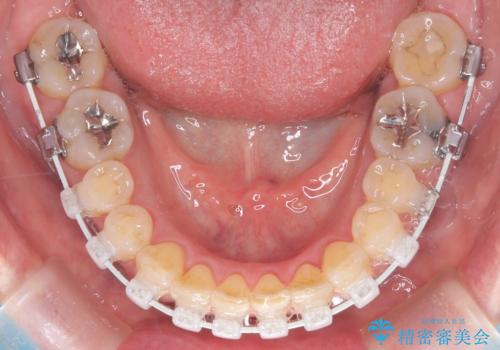

今回の矯正治療では、歯の色に近い目立たない審美ブラケットとワイヤーを使用しました。

スペース確保のために、まず奥歯全体をわずかに後方へ動かす遠心移動を実施し、前歯を並べるためのスペースを確保。さらに、安全性に配慮しながら歯の側面をわずかに削るIPRを併用し、デコボコを解消しました。